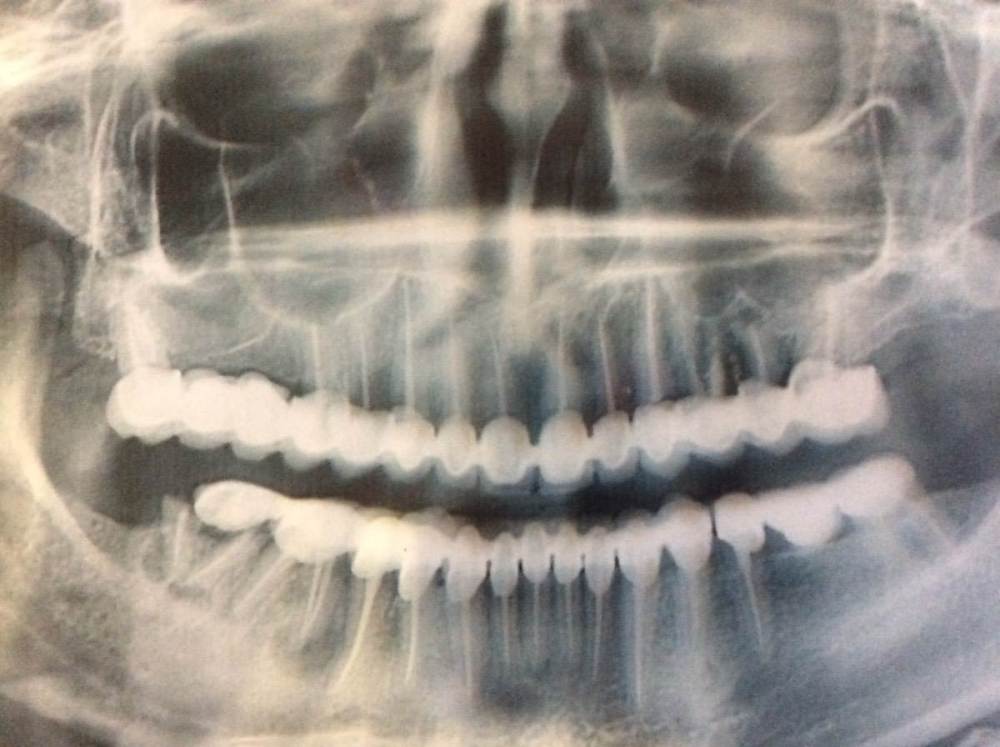

Idunno Опубликовано 5 июля, 2023 Поделиться Опубликовано 5 июля, 2023 (изменено) Здравствуйте, уважаемые доктора. 8 лет назад уже обращалась на этот форум и мне здесь очень помогли. Хотелось бы услышать профессиональное мнение еще раз. У меня тотальное протезирование. Металлокерамика. Установлены две дуги вверху и внизу. Единичные коронки установить не было возможности по ряду причин (описывала их в своей теме 8 лет назад). Через год после установки у меня разгерметизировалась одна из коронок внизу. Мой стоматолог (это было в другой стране) просто отпилил часть дуги и сделал новые коронки на 3 зуба, слитные. Потом будет понятно, почему я об этом упомянула. В 2020 году у меня откололась керамика внизу уже с другой стороны. Это был год Ковида и было не до стоматологии в тот момент. Следом за этим сколом в течение месяца произошли отколы еще на двух соседних зубах. И вот с этим всем я, наконец, добралась до врача. Мы сделали снимок. На нем понятно, что корень правой нижней семерки уже отдельно от зуба и ее нужно удалять. С этим мы с доктором пришли к консенсусу. Но когда я спросила, можно ли чтобы исправить сколы на соседних коронках так же отпилить часть дуги, как это было сделано с противоположной стороны - врач сказал нет. Надо снимать всю дугу (без тех трех слитных коронок) и делать дугу заново. Почему нельзя сделать отпил 3 единиц я так и не поняла. На мой аргумент, что хотелось бы исправить - он ответил: «Ну их же не видно». Да, их не видно. Но я же о них знаю. И хочу исправить. Ведь это тоже эстетический момент. Кроме того, я сомневаюсь что момент это только лишь эстетический, так как из-за сколов геометрия прикуса тоже меняется. Не просто так же у меня скололись еще 2 коронки. Также разногласия возникли по второму вопросу. Поскольку правую семерку надо удалять. И тут он готов пилить мост с ней, то я заикнулась что хотела бы на ее месте установить имплант. Потому что когда мы удалим семерку, внизу у меня останется 6 зубов. А сверху будет 8. Я хотела бы восстановить внизу зубной ряд. На что мне доктор сказал - это не критично. Вышла я от врача с невнятным осадком. Вроде бы его хвалили те, кто мне его порекомендовал. Но я на себя примерила его предложения- оставить сколотые коронки и уйти без импланта - и я понимаю, что мне это не подходит. Плюс, он сказал что есть киста на соседнем с удаляемым зубом. Он сейчас под коронкой со сколом. Может быть, пока оставить эту коронку? Не менять? Пожалуйста, посоветуйте что делать. Удалять зуб с отломанным корнем еду завтра - это в любом случае делать надо. А вот что дальше... снимок прилагаю. Заранее всем спасибо за ответы. Изменено 5 июля, 2023 пользователем Idunno Ссылка на комментарий